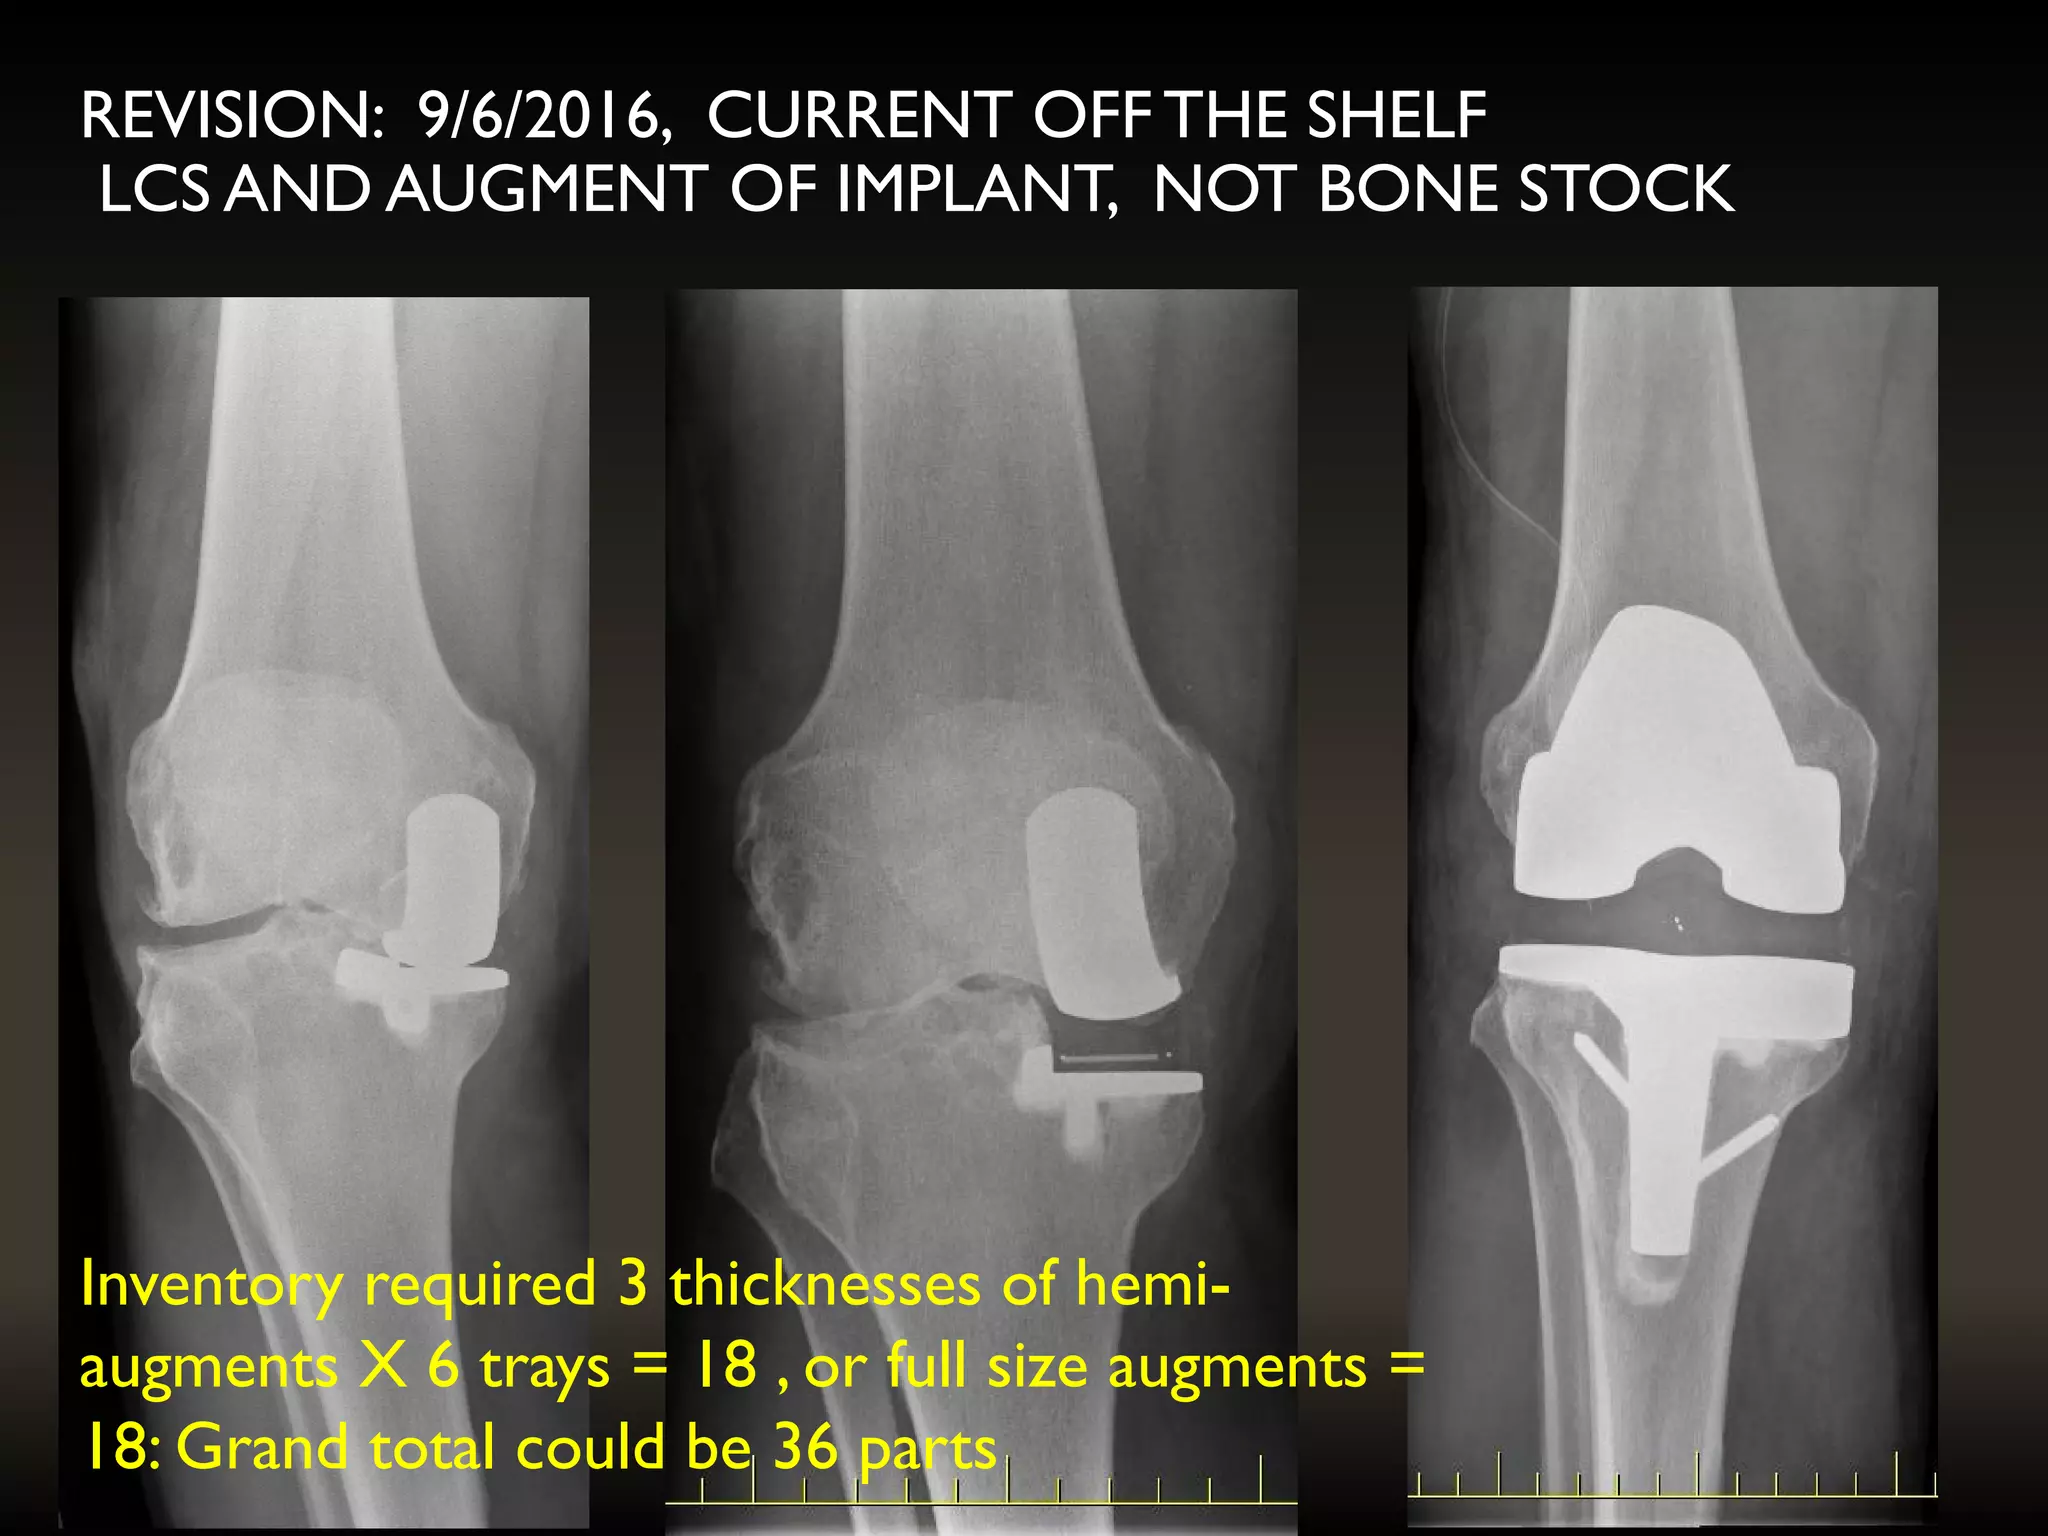

REVISION: 9/6/2016, CURRENT OFF THE SHELF

LCS AND AUGMENT OF IMPLANT, NOT BONE STOCK

Inventory required 3thicknesses of hemi- augments X 6 trays = 18 , or full size augments = 18: Grand total could be 36 parts REVISION: 9/6/2016, CURRENT OFF THE SHELF LCS AND AUGMENT OF IMPLANT, NOT BONE STOCK

PRE-OP PLANNING ANDCT SCANNING • Tray size would be known • Augment thickness planned and manufactured • Bearing thickness still not predictable • Saving on inventory required

Inventory required 3 thicknesses of hemi-

augments X 6 trays = 18 , or full size augments =

18: Grand total could be 36 parts